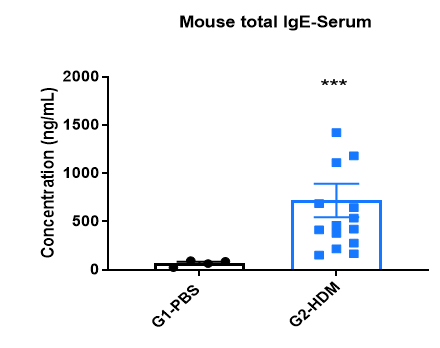

IgE Induction in Serum of Asthmatic Mice

Increased IgE levels in serum of OVA-induced mice compared with controls. Serum was isolated at the end of the experiment and concentrations of OVA-specific IgE (A) and serum total IgE (B) were measured using ELISA.

Increased IgE levels in serum of HDM-induced mice compared with controls. Serum was isolated at the end of the experiment and concentrations of total IgE were measured using ELISA.